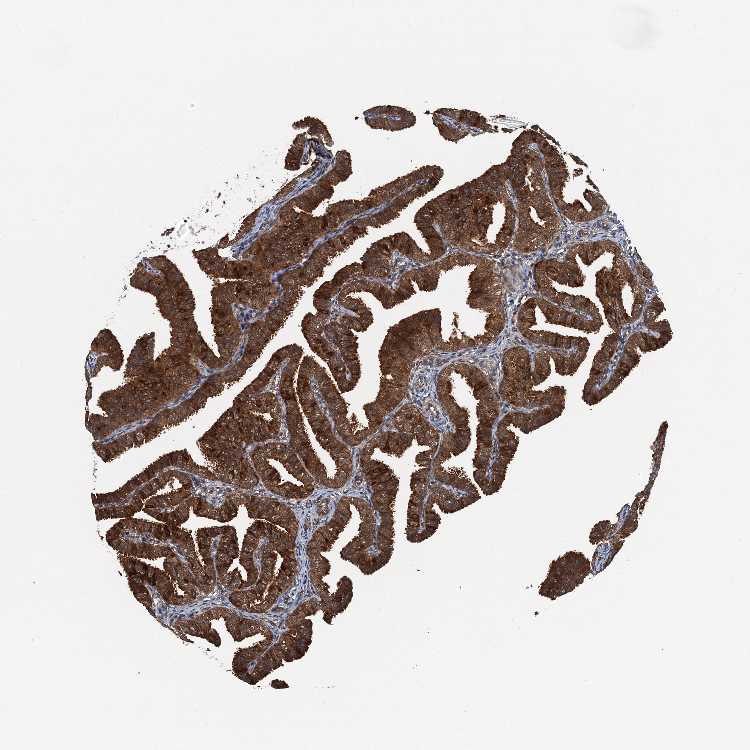

FALLOPIAN TUBE - Antibody stainingi

Antibody staining in the annotated cell types in the current human tissue is reported as not detected, low, medium, or high, based on conventional immunohistochemistry profiling in selected tissues. This score is based on the combination of the staining intensity and fraction of stained cells.

Each image is clickable and will lead to virtual microscopy that enables deeper exploration of all samples and also displays staining intensity scores, fraction scores and subcellular localization as well as patient and tissue information for each sample.

Antibody HPA039371Antibody HPA040174

Ciliated cells (cell body) -High

Ciliated cells (cilia axoneme) -Not detected

Ciliated cells (ciliary rootlets) -Not detected

Ciliated cells (tip of cilia) -Medium

Glandular cells High-

Non-ciliated cells -High